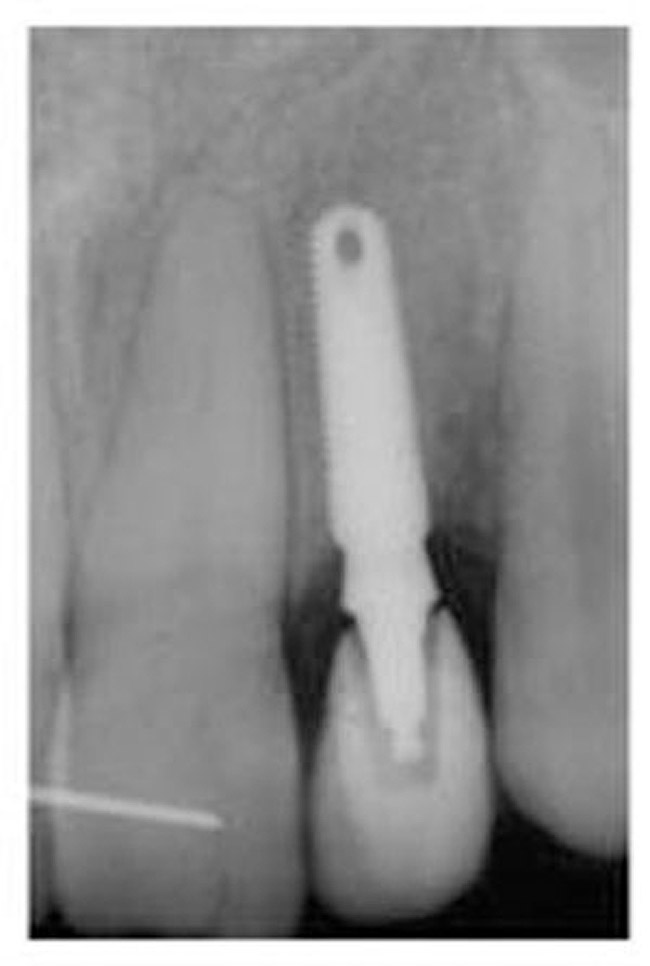

Figure 16  Immediate postoperative digital periapical; right lateral incisor.

Figure 16

Figure 17  Immediate postoperative digital periapical; left lateral incisor.

Figure 17

Conversion of the surgical guide to the esthetic provisional was then completed by retrofitting the surgical guide with restorative composite, and then placing the guide back over the provisional copings that were seated on the abutment portion of the one-piece implants, and curing the surgical guide with a curing light (Figure 12). The guide was then reviewed, with the provisionals in the guide, then removal of the provisionals from the vacuform portion of the guide allowed for correction of the marginal portion of the provisionals using a flowable composite material. Shaping the line angles and emergence profile of the provisionals allowed for the proper contours of the provisional to be accomplished (Figure 13). The provisionals were then cemented with a strong temporary cement. The immediate postoperative clinical view can be seen in Figure 14 and Figure 15. The provisionals were immediate, non-functional restorations in centric occlusion and relation, and lateral right and left excursive movements. Figure 16 and Figure 17 show the immediate postoperative radiographic view. Note how the 3-mm diameter implant allows for the adequate space between the root surfaces and the implants placed.